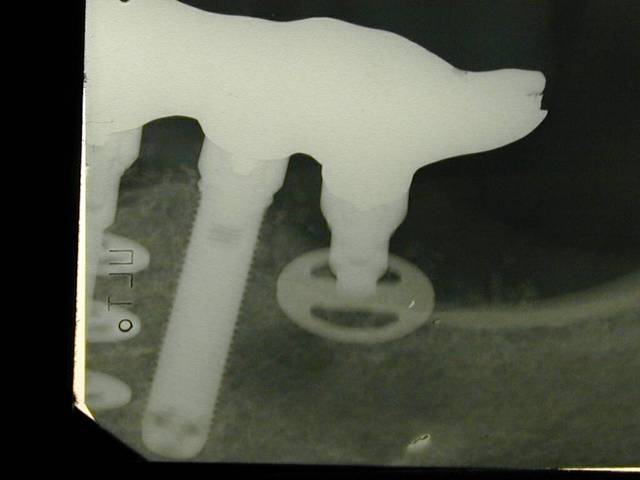

Periapicale 2 a9vo89 - Eugenol

Pour curieux impécunieux s'abstenir, les 35 et 45 répondent aux critères définissant l'ostéointégration, désolé! Quant à "pas d'os en mésial", le truc ovale noir que tu vois sous l'implant, c'est un machin que l'on appelle le trou mentonnier, t'inquiètes pas.

On voit bien en effet la confirmation bi-latérale sur la periapicale